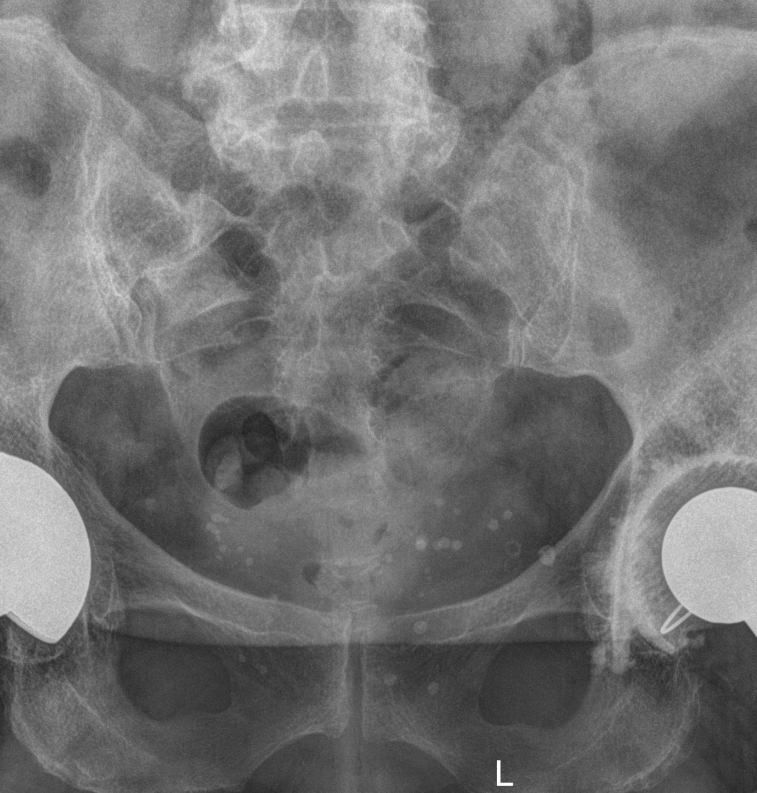

Для диагностики сочленения прибегают к рентгенографии, причем снимки делают с обеих сторон, чтобы можно было сравнить здоровую и измененную сторону. Для более детального исследования применяют МРТ.

Что покажет рентген крестцово-подвздошного сочленения?

• Изменения в состоянии рентгеновской суставной щели ― расширение, сужение, сращение;

• Изменения суставной поверхности ― нечеткость контуров, уплотнение, эрозии;

• Изменения в костной ткани ― участки деструкции, воспаление, склероз;

• Наличие кист и других новообразований;

• Изменения в мягких тканях